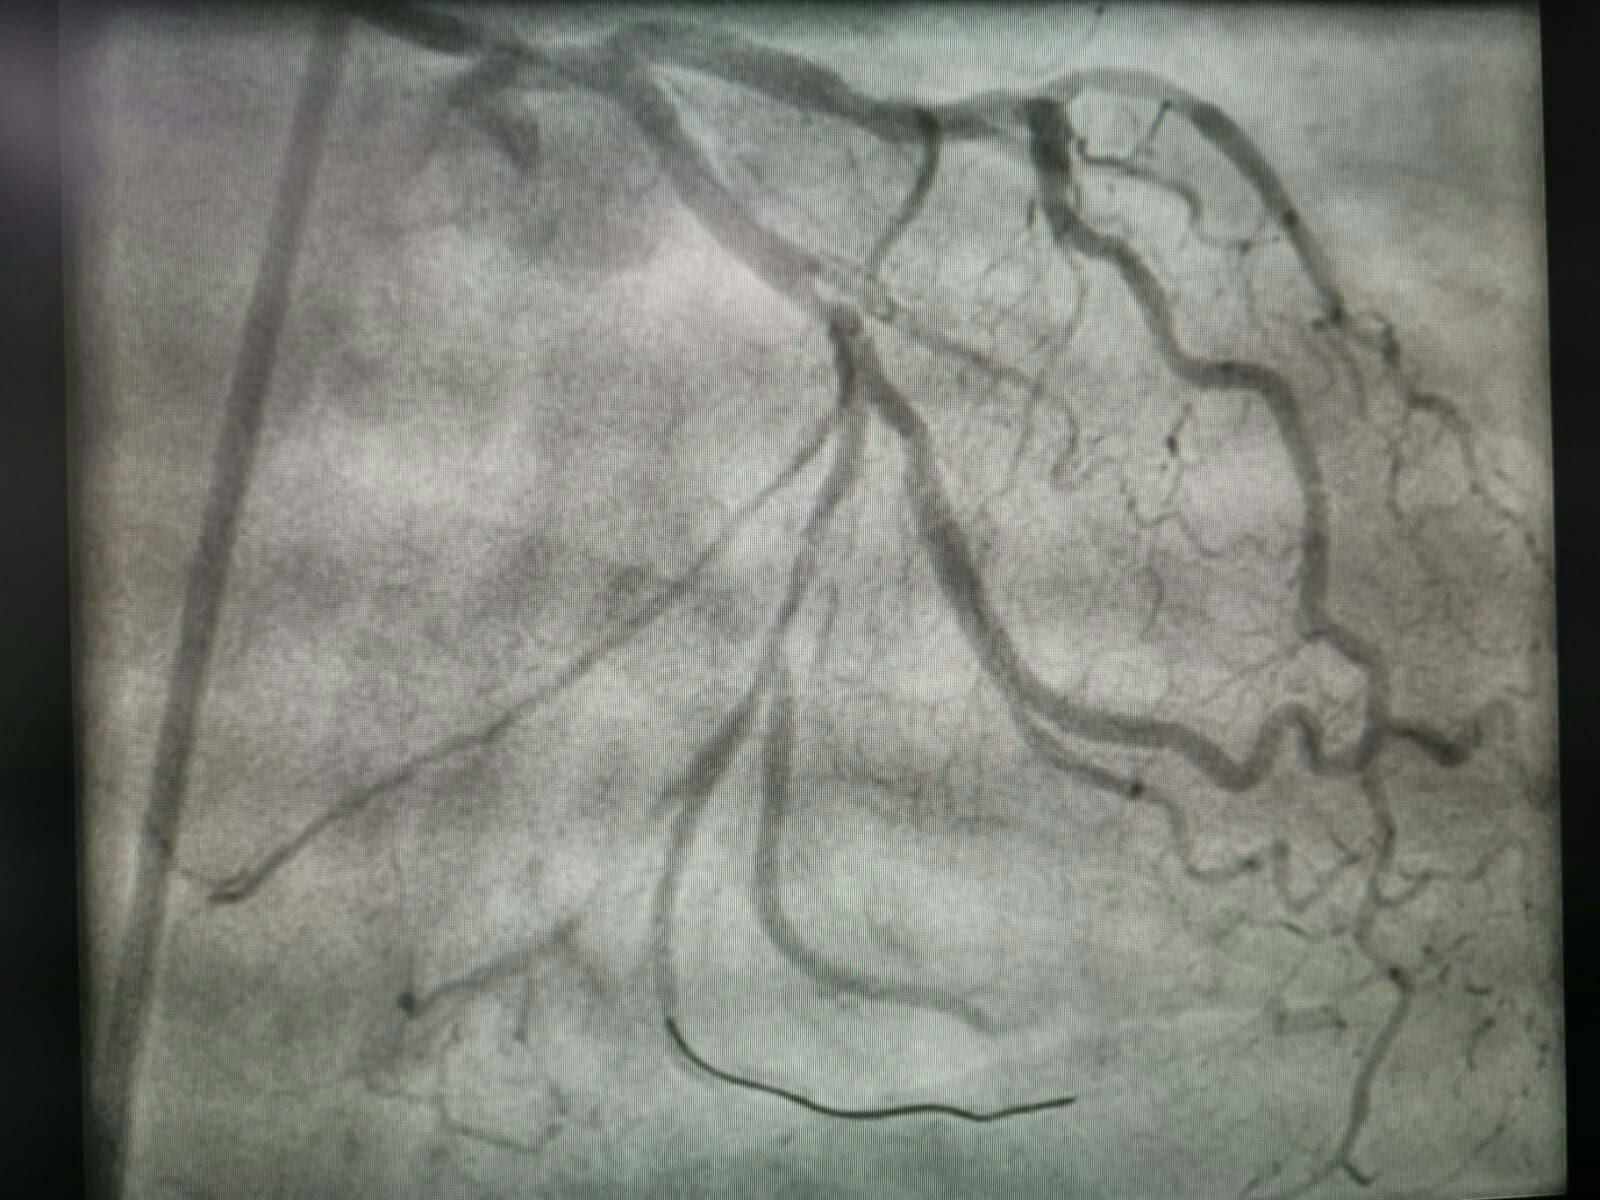

În anul 2019, în cadrul Compartimentului de Cardiologie Intervențională a Spitalului Județean de Urgență Buzău, au fost efectuate un număr de 163 de intervenții coronariene la pacienți cu afecțiuni cardiovasculare acute.

În luna ianuarie a acestui an, 18 pacienți au beneficiat de aceste proceduri intervenționale, doi dintre aceștia - unul în vârstă de 49 de ani iar celălalt de 68 de ani - au fost diagnosticați cu boală arterială periferică și au beneficiat de procedura de angioplastie periferică percutană la nivelul membrelor inferioare.